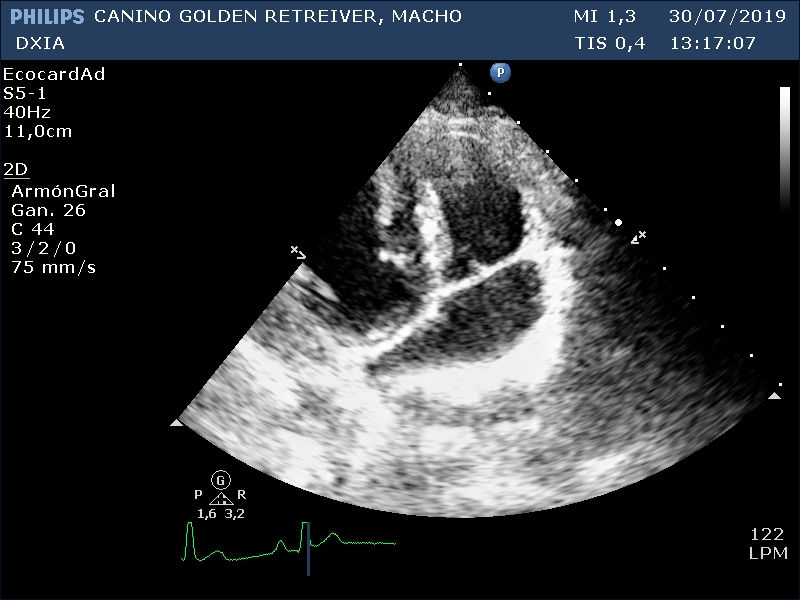

Dos imágenes obtenidas durante el estudio ecográfico:

Ecocardiograma DXIA Scott

Corte apical craneal izquierdo optimizando cámaras derechas y VT. No se detecta la existencia de Filarias adultas cardíacas ni dilatación en cámaras derechas.

Doppler de la VP donde se observa flujo laminar con velocidad máxima de la pulmonar dentro de valores normales para la especie canina.

Conclusión del estudio ecocardiográfico

• Válvulas cardíacas normoimplantadas sin cambios morfológicos ni hemodinámicos significativos. No se detectan jets turbulentos. Doppler (2D, MM, FW Y CW) valvulares normales.

• No dilatación de cámaras ni cambios en grosores de las paredes cardíacas.

• No cambios compatibles con existencia de HP.

• Función sistólica y diastólica conservadas.

Por tanto, estudio compatible con la no existencia de cardiopatía actualmente en dicho paciente. Corazón sano. Se realizan varios cortes ecográficos debido a que el paciente ha dado positivo en un test a Filaria y se descarta la existencia de filarias adultas cardíacas en el momento del estudio o cambios compatibles con hipertensión pulmonar.